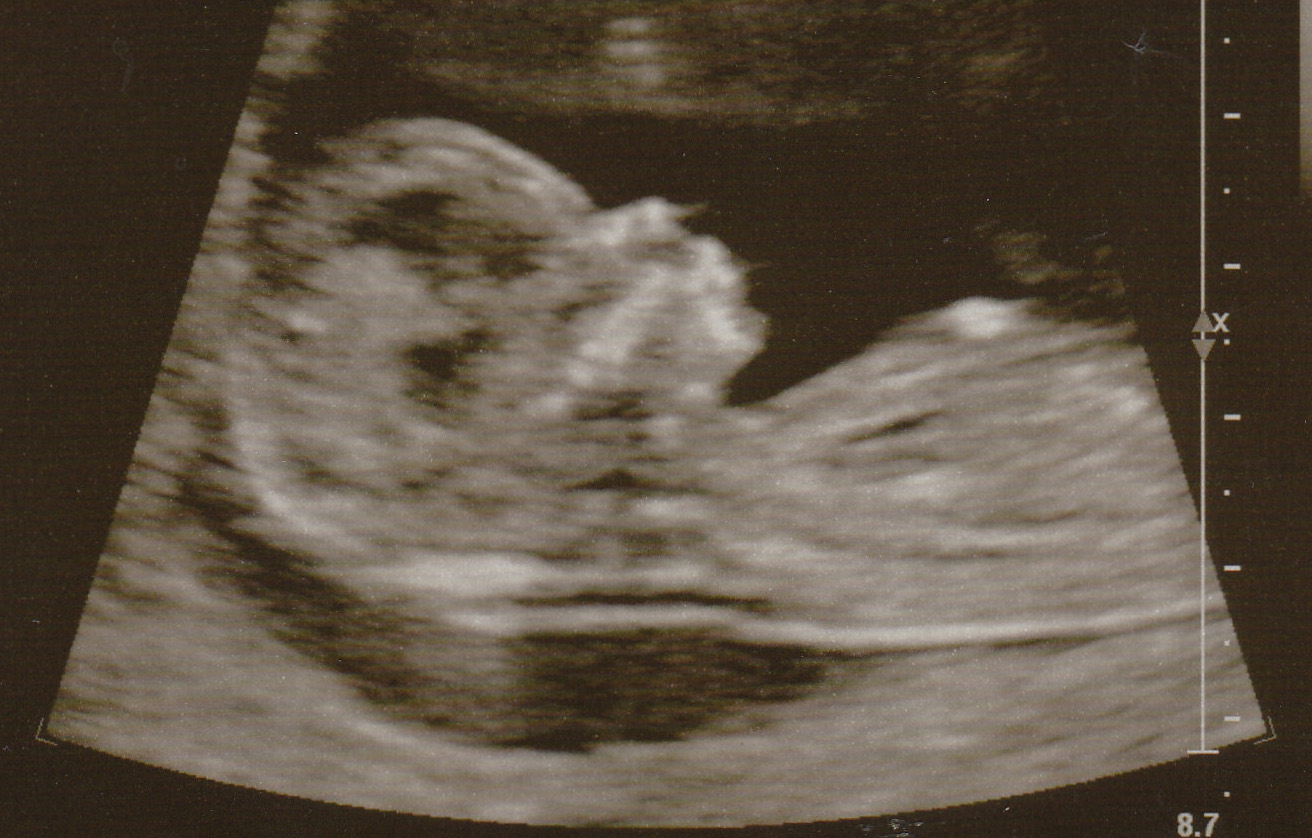

Twin girls H & E were born prematurely at 24 weeks 3 days gestation in the summer of 2004. At birth H was 1 lb 3.5 oz, 11.5", E 1 lb 5.5 oz, 12". This is their story...